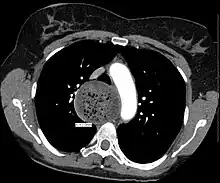

a) Dilatation in the middle esophagus b) achalasia with esophageal dilatation -

An axial CT image showing marked dilatation of the esophagus in a person with achalasia. -